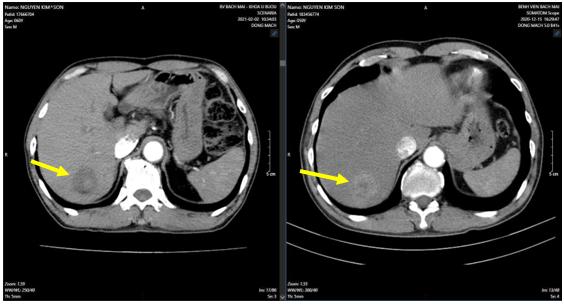

- Tháng 3/2025: Hình ảnh u phân thùy sau gan phải, kích thước 28x38mm, hiện còn tăng sinh mạch (Sau TACE lần 3). Sỏi túi mật. Sỏi thận hai bên.

Hình 3: U gan sau nút mạch lần 3, vào tháng 03/2025 (bên trái, mũi tên vàng) so với trước khi nút mạch lần 3 vào tháng 02/2025 (bên phải, mũi tên vàng)